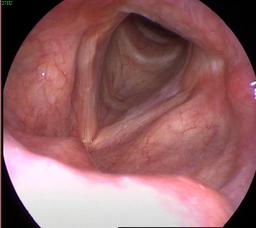

بیوگرافی دکتر دشتله: دکتری تخصصی(Ph.D) گفتاردرمانی دانشگاه علوم پزشکی تهران، با ۱۴ سال تجربه تدریس و کار بالینی تخصصی در زمینه درمان دیسفاژی، مرکز استروبوسکوپی(عکسبرداری)حنجره در تهران، تصویربرداری حنجره، مشکلات صوت و حنجره، چکاپ حنجره و معاینه تارهای صوتی. همچنین ایشان بصورت پیوسته تورهای بلع درمانی (DSRT) در دانشگاه های علوم پزشکی را برگزار میکنند.

کلینیک جامع گفتاردرمانی و کاردرمانی ذهنی، دکتر متخصص بلع در تهران| کلینیک استروبوسکوپی حنجره در تهران با مجوز وزارت بهداشت| عکس حنجره تهران|لارنگوسکوپی حنجره در تهران|تصویربرداری حلق و حنجره در تهران|بهترین لارنگوسکوپی حنجره در سعادت آباد|شهرک غرب| بهترین استروبوسکوپی تهران| متخصص صدا و حنجره تهران| بیوگرافی معاینه حنجره و استروبوسکوپی تارهای صوتی تهران| درمان تخصصی بلع تهران| بهترین دکتر بلع تهران| دکتر متخصص گفتاردرمانی تهران| متخصص گفتاردرمانی کودکان در تهران|متخصص ندول و پولیپ حنجره در تهران|عکس رنگی حنجره|عکس تارهای صوتی|عکس حلق و گلو|عکسبرداری از حنجره|عکس برداری تارهای صوتی|عکس حنجره در غرب تهران|عکس حنجره در سعادت آباد|کلینیک عکس از حنجره در شهرک غرب|مرکز تصویربرداری حنجره در تهران

✅استروبوسکوپی حنجره در تهران، عکس حنجره در تهران

✳️استروبوسکوپی (عکس برداری رنگی) از حنجره در تهران